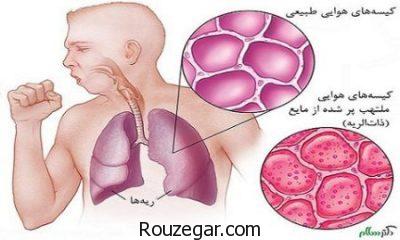

ذات الریه یا سینه پهلو اصطلاح عمومی است که برای توضیح بیماری های التهابی ریه به کار می رود. این بیماری معمولا به این دلیل ایجاد می شود که حفره های شش، کیسه های هوا در ریه ها، از چرک و مخاط پر می شوند. اما سینه پهلو می تواند به قسمت های مختلفی از ریه ها آسیب بزند. التهاب حفره های شش، توانایی ریه ها در گرفتن اکسیژن از هوا را محدود می کنند و درنتیجه موجب ناتوانی سیستم گردش خون می شود. مشکلات دیگری هم ممکن است اتفاق بیفتد. مثلا وقتی باکتری وارد خون می شود یا ریه ها به شدت ملتهب شده و بسته می شوند.